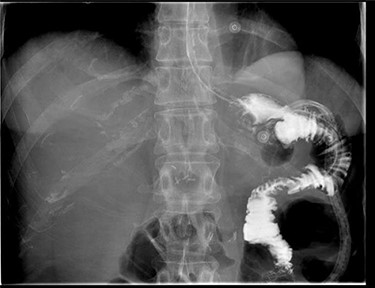

A repeat CT scan was performed, this time with oral contrast, which revealed a large gastrocolonic fistula into the transverse colon (Fig. 1). The patient underwent a gastroscopy and colonoscopy (Fig. 2A–C) which visually confirmed a 50 mm gastrocolonic fistula with a caliber sufficient to allow the passage of a colonoscope with relative ease (~13 mm), and no signs of active Crohn’s disease.

Coronal and axial slices of a CT abdomen/pelvis with oral contrast demonstrating a gastrocolonic fistula.